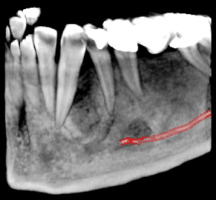

Секторни зъбни снимки

Зъбни снимки

Това са най-разпространените зъбни снимки. За да имат добра диагностична стойност, те трябва да обхващат целия зъб - коронката, корена и прилежащата около него кост. Така лекарите по дентална медицина могат да констатират наличието на много заболявания като кариеси, грануломи, кисти, пародонтални проблеми, както и да проследяват развитието на кореново лечение или интеграцията на поставените импланти.